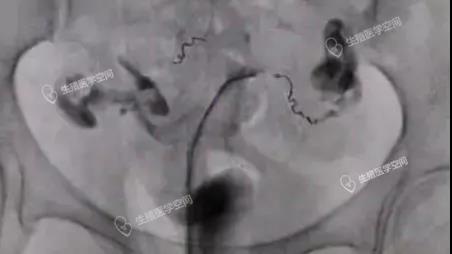

一、评估一下输卵管的粘膜功能是否正常,如果伞部和壶腹部粘膜功能大致正常(图1),就做输卵管积水伞端造口术。如果输卵管粘膜少或无,导致输卵管生殖功能丧失(图2),就直接做试管婴儿。

放射科的子宫输卵管造影是诊断输卵管积水最准确直观的无创检查方法,同时还可以对输卵管粘膜功能做一个初步评估。